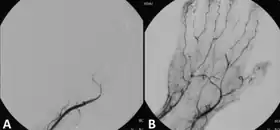

![]() Angiograph before and after thrombolytic therapy in a case of acute limb ischemia. | |

- Acute limb ischaemia[7]